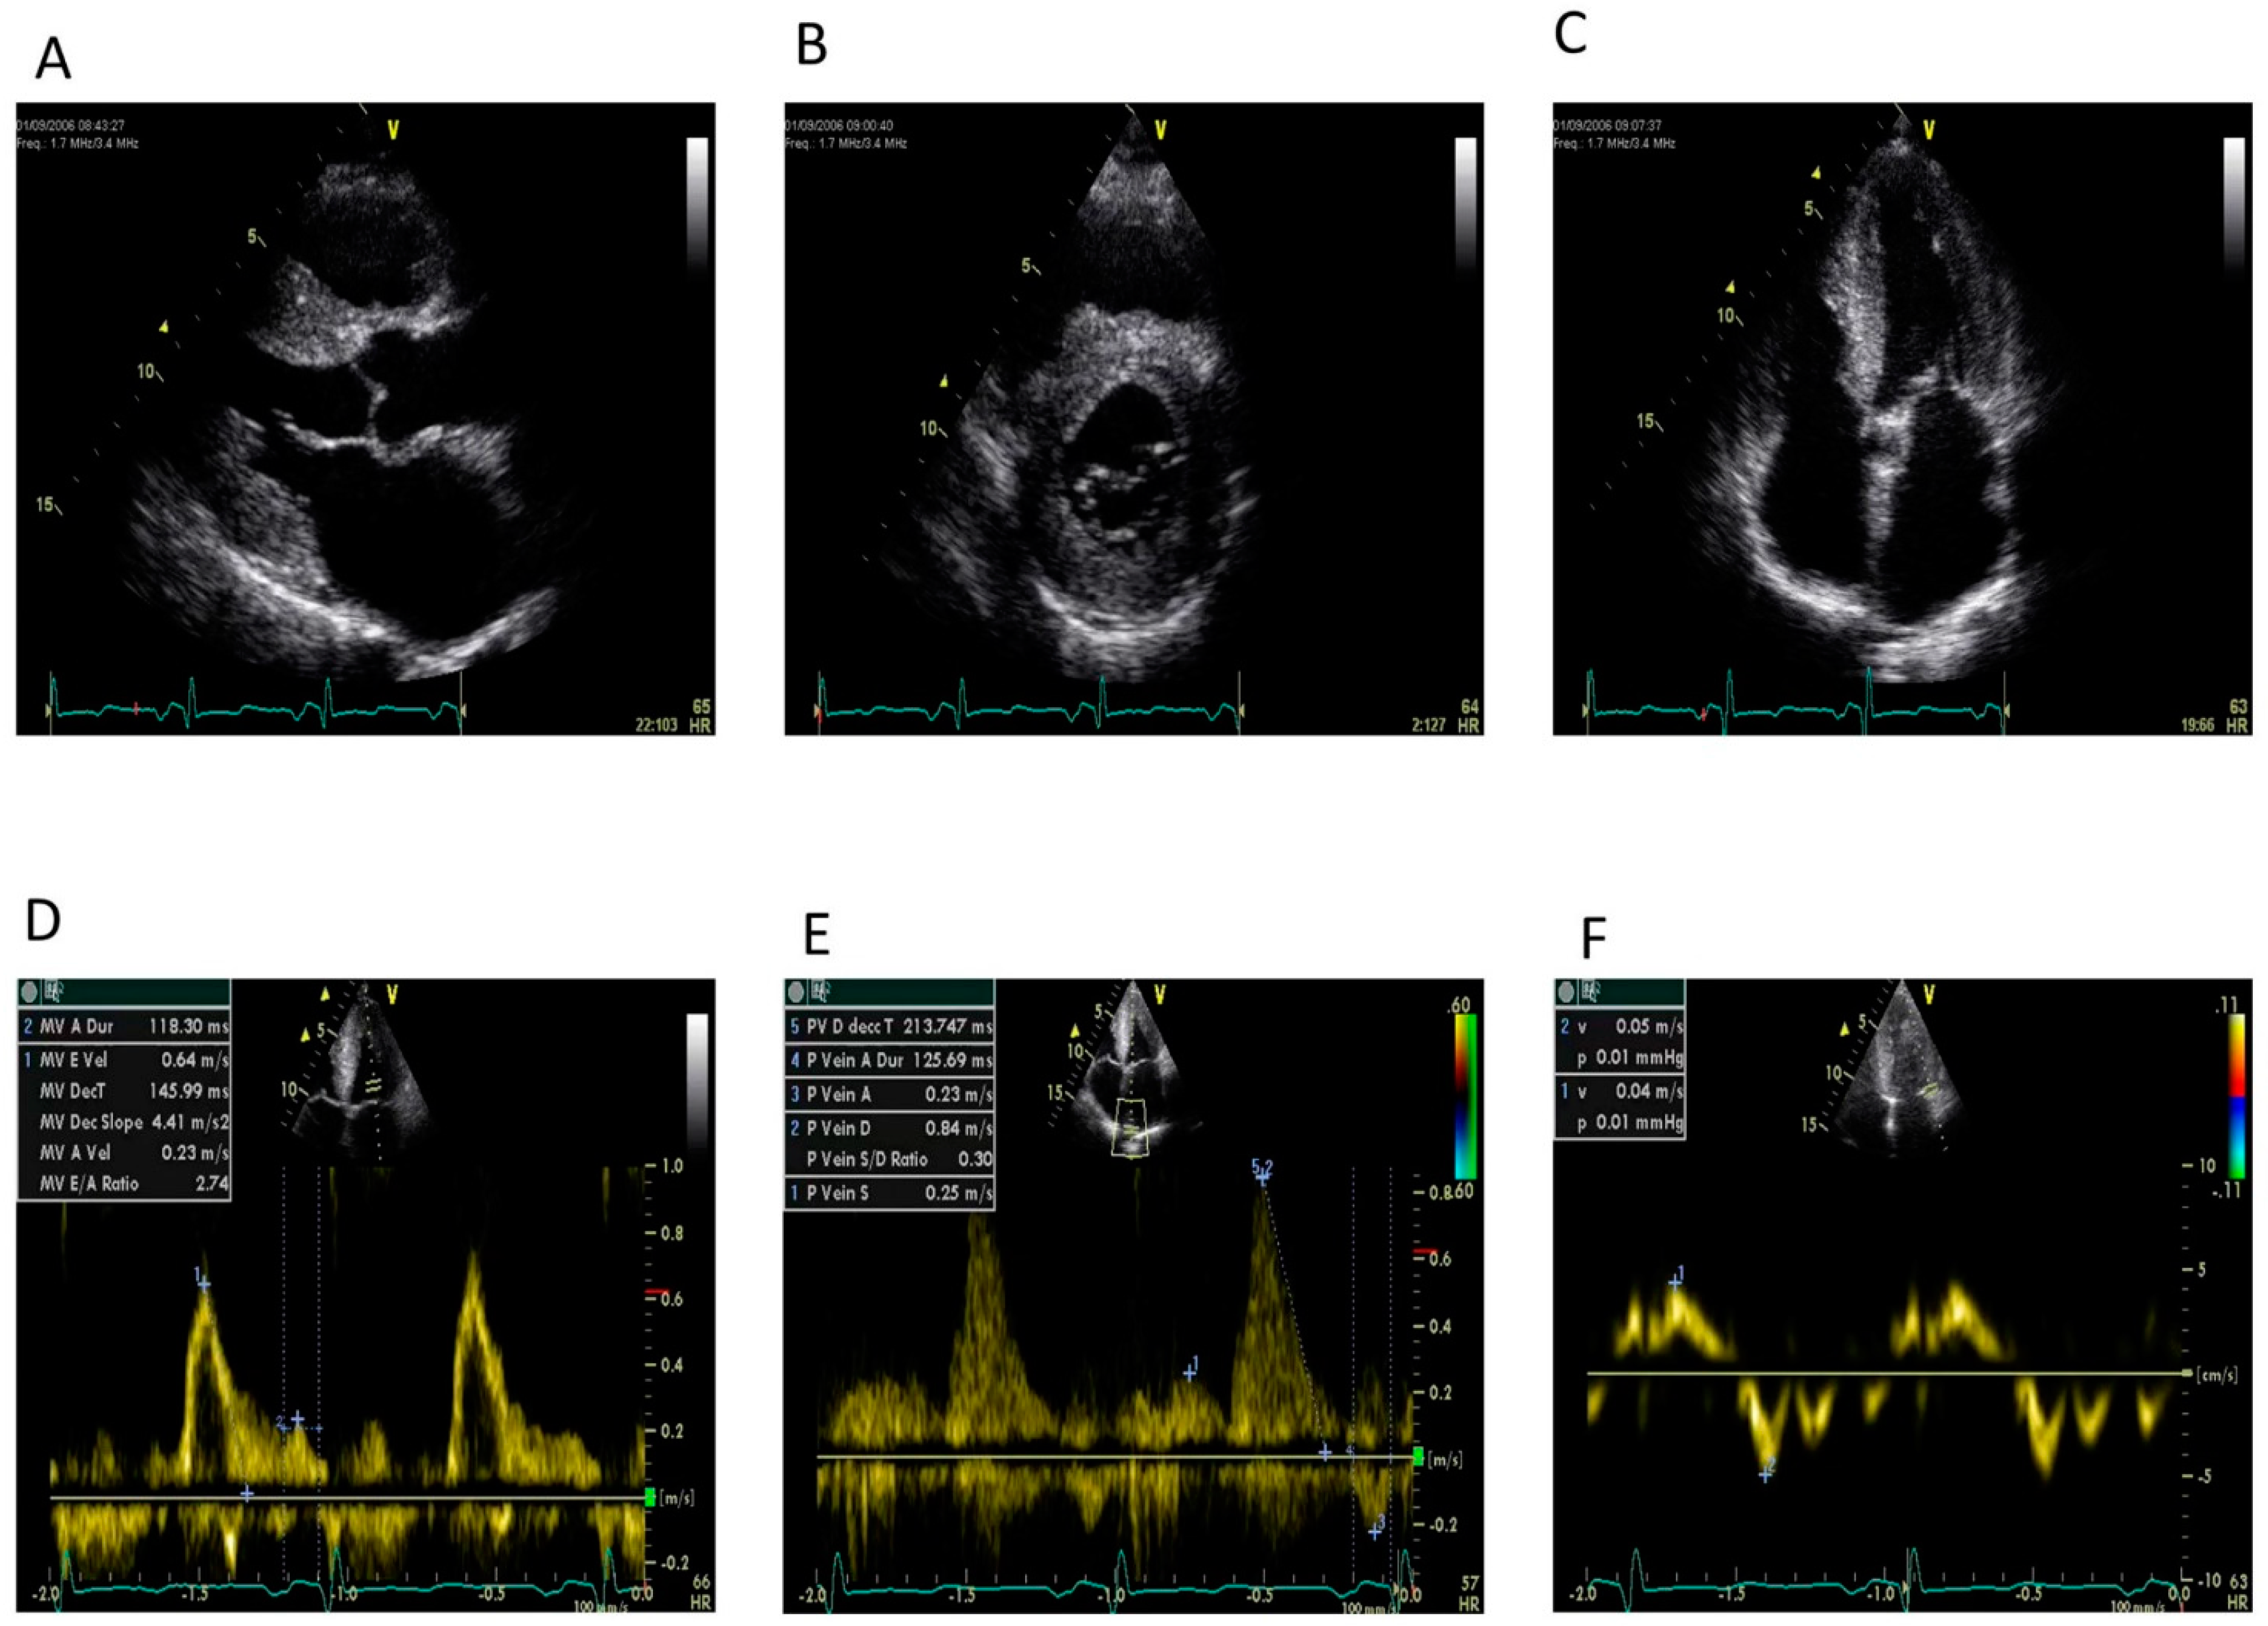

Figure 3.

Sequence of still images showing typical echocardiographic features of cardiac amyloidosis. (A): Two-dimensional (2-D) parasternal long axis showing an increase of left ventricular wall thickness—in both the interventricular septum and the posterior wall (concentric hypertrophy)—and left atrial dilatation. (B): Two-dimensional parasternal short axis. (C): Two-dimensional apical four-chamber view. In B and C, it is possible to highlight not only the left ventricular hypertrophy but also the biatrial dilatation. (D): Pulsed wave Doppler of mitral inflow showing a restrictive pattern at transmitral flow: increase in E/A ratio and normal E wave deceleration time with a marked reduction in transmitral A wave velocity. (E): Pulsed wave Doppler of pulmonary vein inflow showing marked diastolic prominence and increased duration and peak velocity of atrial reversal compared with the transmitral signal. (F): Pulsed tissue Doppler of the lateral mitral annulus showing marked reduction in apical systolic and diastolic velocities (normal velocities: >6 cm/s and >8 cm/s, respectively). Images courtesy of Professor Elliott, University College London, UK.